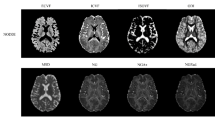

Independent component #0 (IC0) explained 45.6% amount of the total variance in the data (Supplementary Fig. S3), captured common variance across all of the eight diffusion MRI measures (Fig. 1) and showed a highly significant effect of diagnosis (corrected for multiple comparisons, F2,158 = 16.5, p < 0.001, Supplementary Fig. S1). Note that although we used a model order of 25 for the present study, post-hoc analyses showed that the main effect of diagnosis for the primary component (IC0) remained stable across a broad range of model orders (Supplementary Fig. S4).

Spatial maps (a) and subject loadings distribution (b) of IC0. The spatial maps represent the thresholded z-scores (3 < |z| < 10). In the spatial maps, the weights (in percentage) indicate the relative contribution of each measure to the component at the group level. In the subject loading plot, the box represents the 25% and 75% quantiles, the horizontal bar in the box representing the median, and the diamond the mean. The plot shows a graded pattern of AD < MCI < SCI.

Eight complementary diffusion MRI indices of the WM microstructure and connectivity were generated for each participant (Supplementary Fig. S12 shows a sample view from one representative dataset). In particular, using a tensor-model fit in FSL, we derived two measures of voxel diffusion anisotropy (fractional anisotropy (FA) and the mode (MO) of the diffusion tensor58) and three diffusivity indices (mean (MD, average of the three eigenvalues), axial (L1, the primary eigenvalue) and radial (RD, mean of the second and third eigenvalues) diffusivity).

Two additional crossing-fiber measures were calculated by fitting a two-fiber diffusion model (bedpostX), referred to as the partial volume or ball-and-stick model59,60,61. The multi-fiber model used here yielded an estimated volume fraction of the dominant (f1) and the non-dominant (f2) fiber orientation, reflecting the diffusion strength along the dominant and non-dominant axes of the diffusion tensor, respectively.

Finally, we calculated whole brain connectivity density maps for each participant by means of probabilistic tractography. Specifically, we performed probabilistic fiber tracking using probtrackx259, which samples the voxelwise posterior probability distributions generated by bedpostx. For each participant and from each voxel inside the entire native space whole brain seed mask, 200 streamlines were followed, resulting in a single 3D-volume tractography map per participant, which we then normalized by dividing it with the total number of streamlines processed for each participant. The normalized value in each voxel represents the likelihood that any streamline will pass through that voxel, which was used as a measure of WM connection density (CDM).